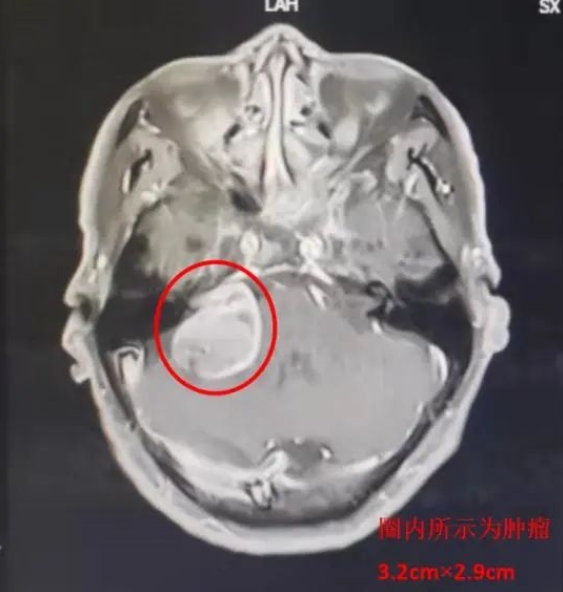

患者马某,69岁,因耳鸣及头晕2年,严重影响日常生活,3月19日就诊于乐鱼手机站入口神经外科一病区。入院诊断:右侧听神经瘤。

3月28日,由主任医师赵金安监台,主治医师段吉强主刀,历时8小时顺利完成手术,术中肿瘤全切、各神经血管完整解剖保留,术中出血约200ml。术后1小时患者即苏醒,生命体征平稳。